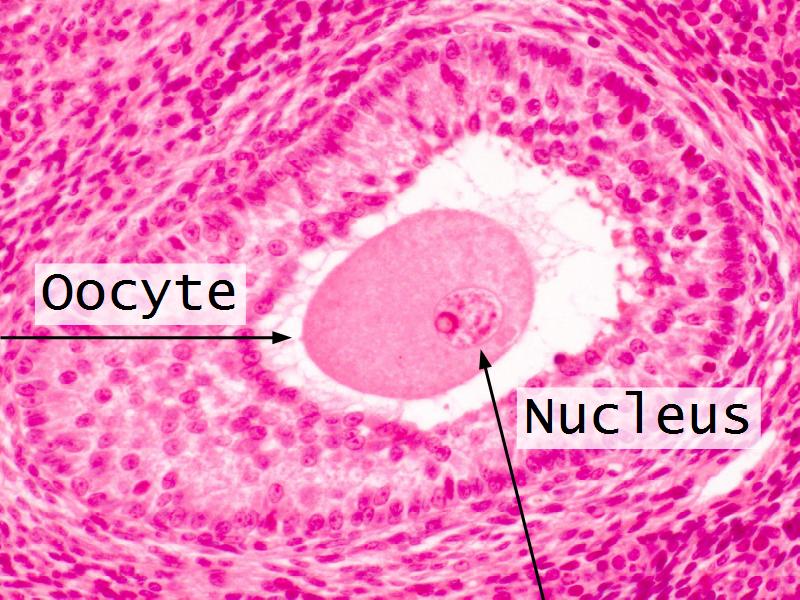

- Ovary

- F3: Granulosa cell

- F3: Granulosa cell = ovarian follicle

- Slide 89/106: Ovary